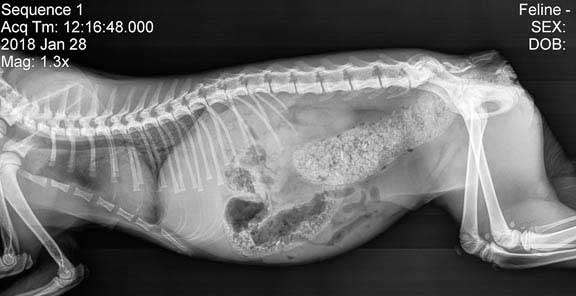

Radiologica Röntgentolk har utgått från chatt med din doktor som har en frågeställning som ska utredas. I detta exempel är det en katt som kan vara förstoppad. En komplett remiss har producerats. Remissens frågeställning tillsammans med röntgenbilder du kan ladda upp kommer att tolkas och generera ett remissvar.

Vi även lagt till att det faktiskt tas röntgenbilder baserat på remissen och AI-doktorns rekomendation baserat på denna. Detta sker självklart inte samtidigt i praktiken då djurägaren först måste komma in till kliniken och göra dessa föreslagna röntgenbilder.